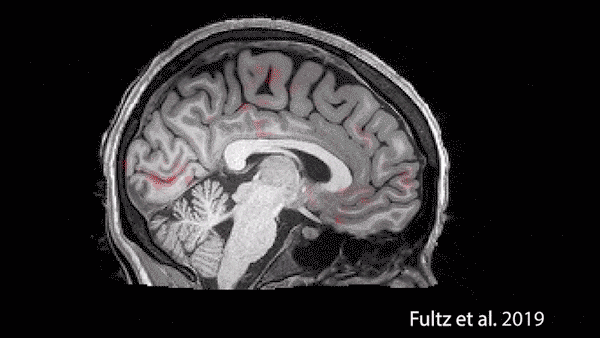

Une très récente étude de 2019 a pu capturer des images de ce qu’il se passe exactement chez les humains, en faisant dormir des gens dans un IRM. Et comme vous pouvez le voir sur la figure 1, ce sont des vagues de fluide qui balaient tout le cerveau à un rythme régulier. Un mécanisme qui a lieu uniquement pendant le sommeil, jamais pendant l’éveil.

Figure 1 : Pendant le sommeil, des vagues de sang (en rouge) alternent

avec des pulsions de fluide cérébrospinal (en bleu). Fultz et al., Science, 2019